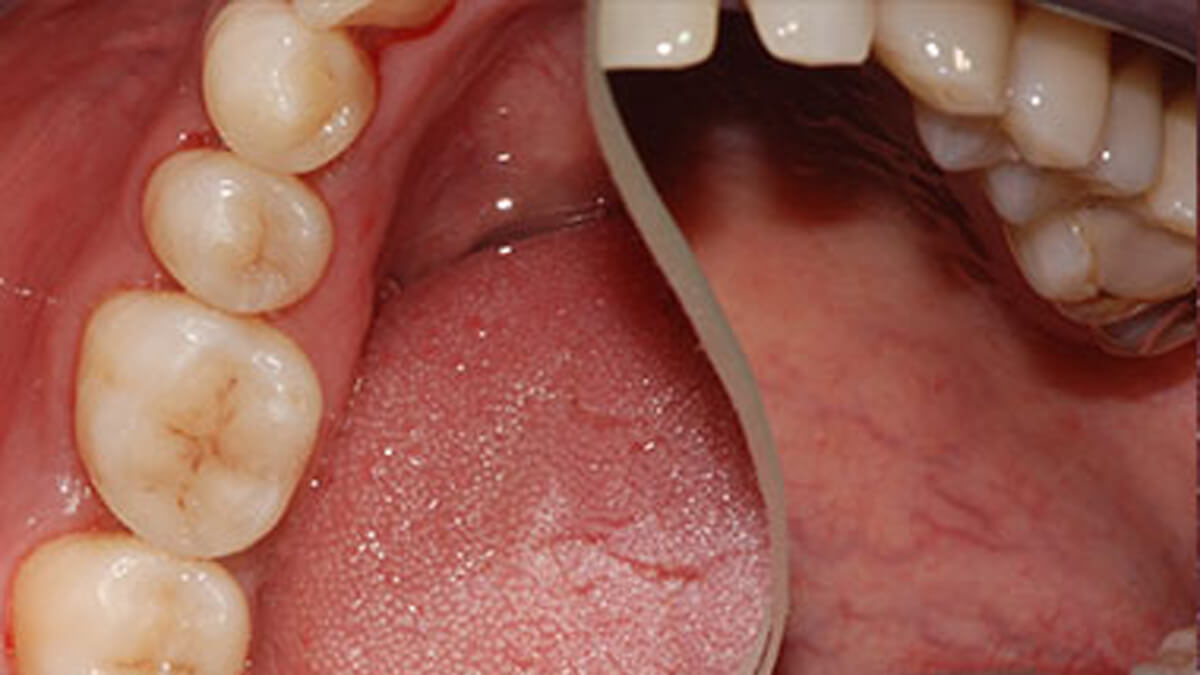

fogszuvasodás kezeléseSzájüregünkben, a fogak felszínén, az ínyen, a nyelvünkön számos baktérium található, melyek fontos szerepet játszanak a biológiai egyensúly fenntartásában. Néhány baktérium azonban a táplálkozásunk során elfogyasztott szénhidrátot képes lebontani úgy, hogy közben sav keletkezik. Ennek következménye, hogy étkezés után csökken szájüregünk pH-értéke, azaz savas közeg alakul ki, amelyet nyálunk semlegesítő hatása egy idő után helyreállít. Abban az esetben, ha gyakran fogyasztunk szénhidráttartalmú ételeket, nincs idő, hogy a savak semlegesítődjenek, ezért hosszan tartó alacsony pH-jú időszakok alakulnak ki, s elkezdődik a fogszuvasodás.

A fogszuvasodás megelőzésének tehát két kulcsfontosságú lépése a megfelelő, alapos tisztítás, valamint a szénhidrátfogyasztás gyakoriságának csökkentése.